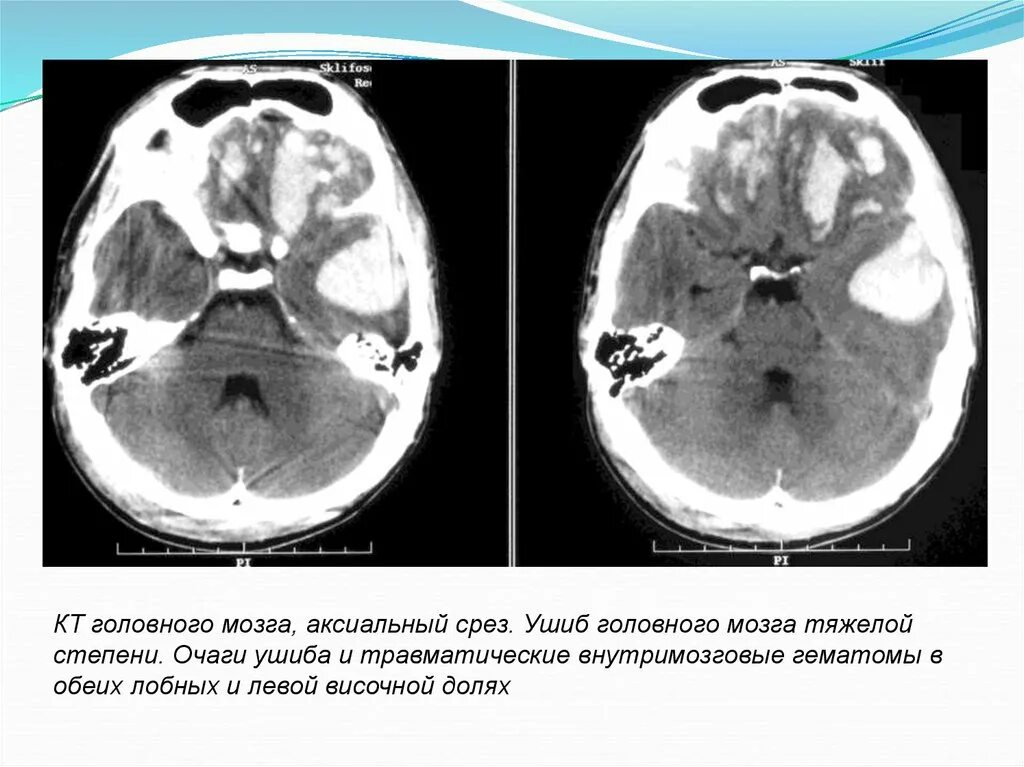

Диффузные изменения срединных структур мозга